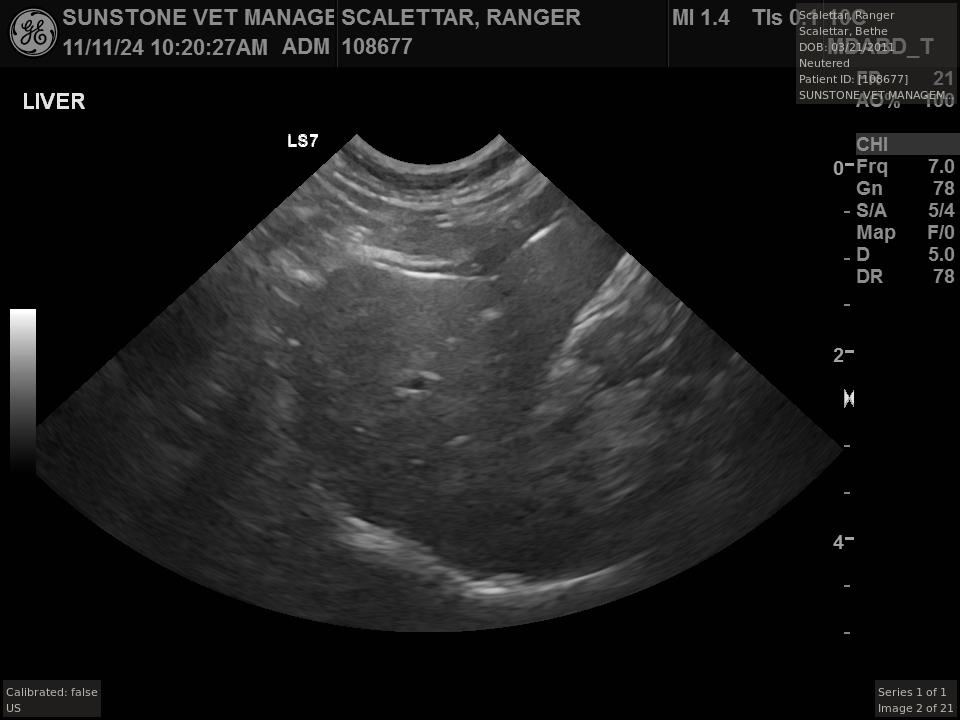

The veterinarian generated a series of images showing different organs and substructures by

changing the position and orientation of the ultrasound transducer. The images were collected

in a defined order, which is repeated from patient to patient, ensuring that nothing is missed. In

Ranger's case, the sonographer collected about twenty images during an examination that

lasted about fifteen minutes.

The sonographer stated that Ranger's ultrasound images were largely normal for an older cat. In particular, they show changes in the kidneys that are commonly noted in geriatric cats and that reflect a risk for the development of chronic kidney disease. However, the images did not show any significant abnormalities in Ranger's stomach, intestines, and associated lymph nodes. Nonetheless, the results did not rule out recurrence of Ranger's small cell lymphoma.